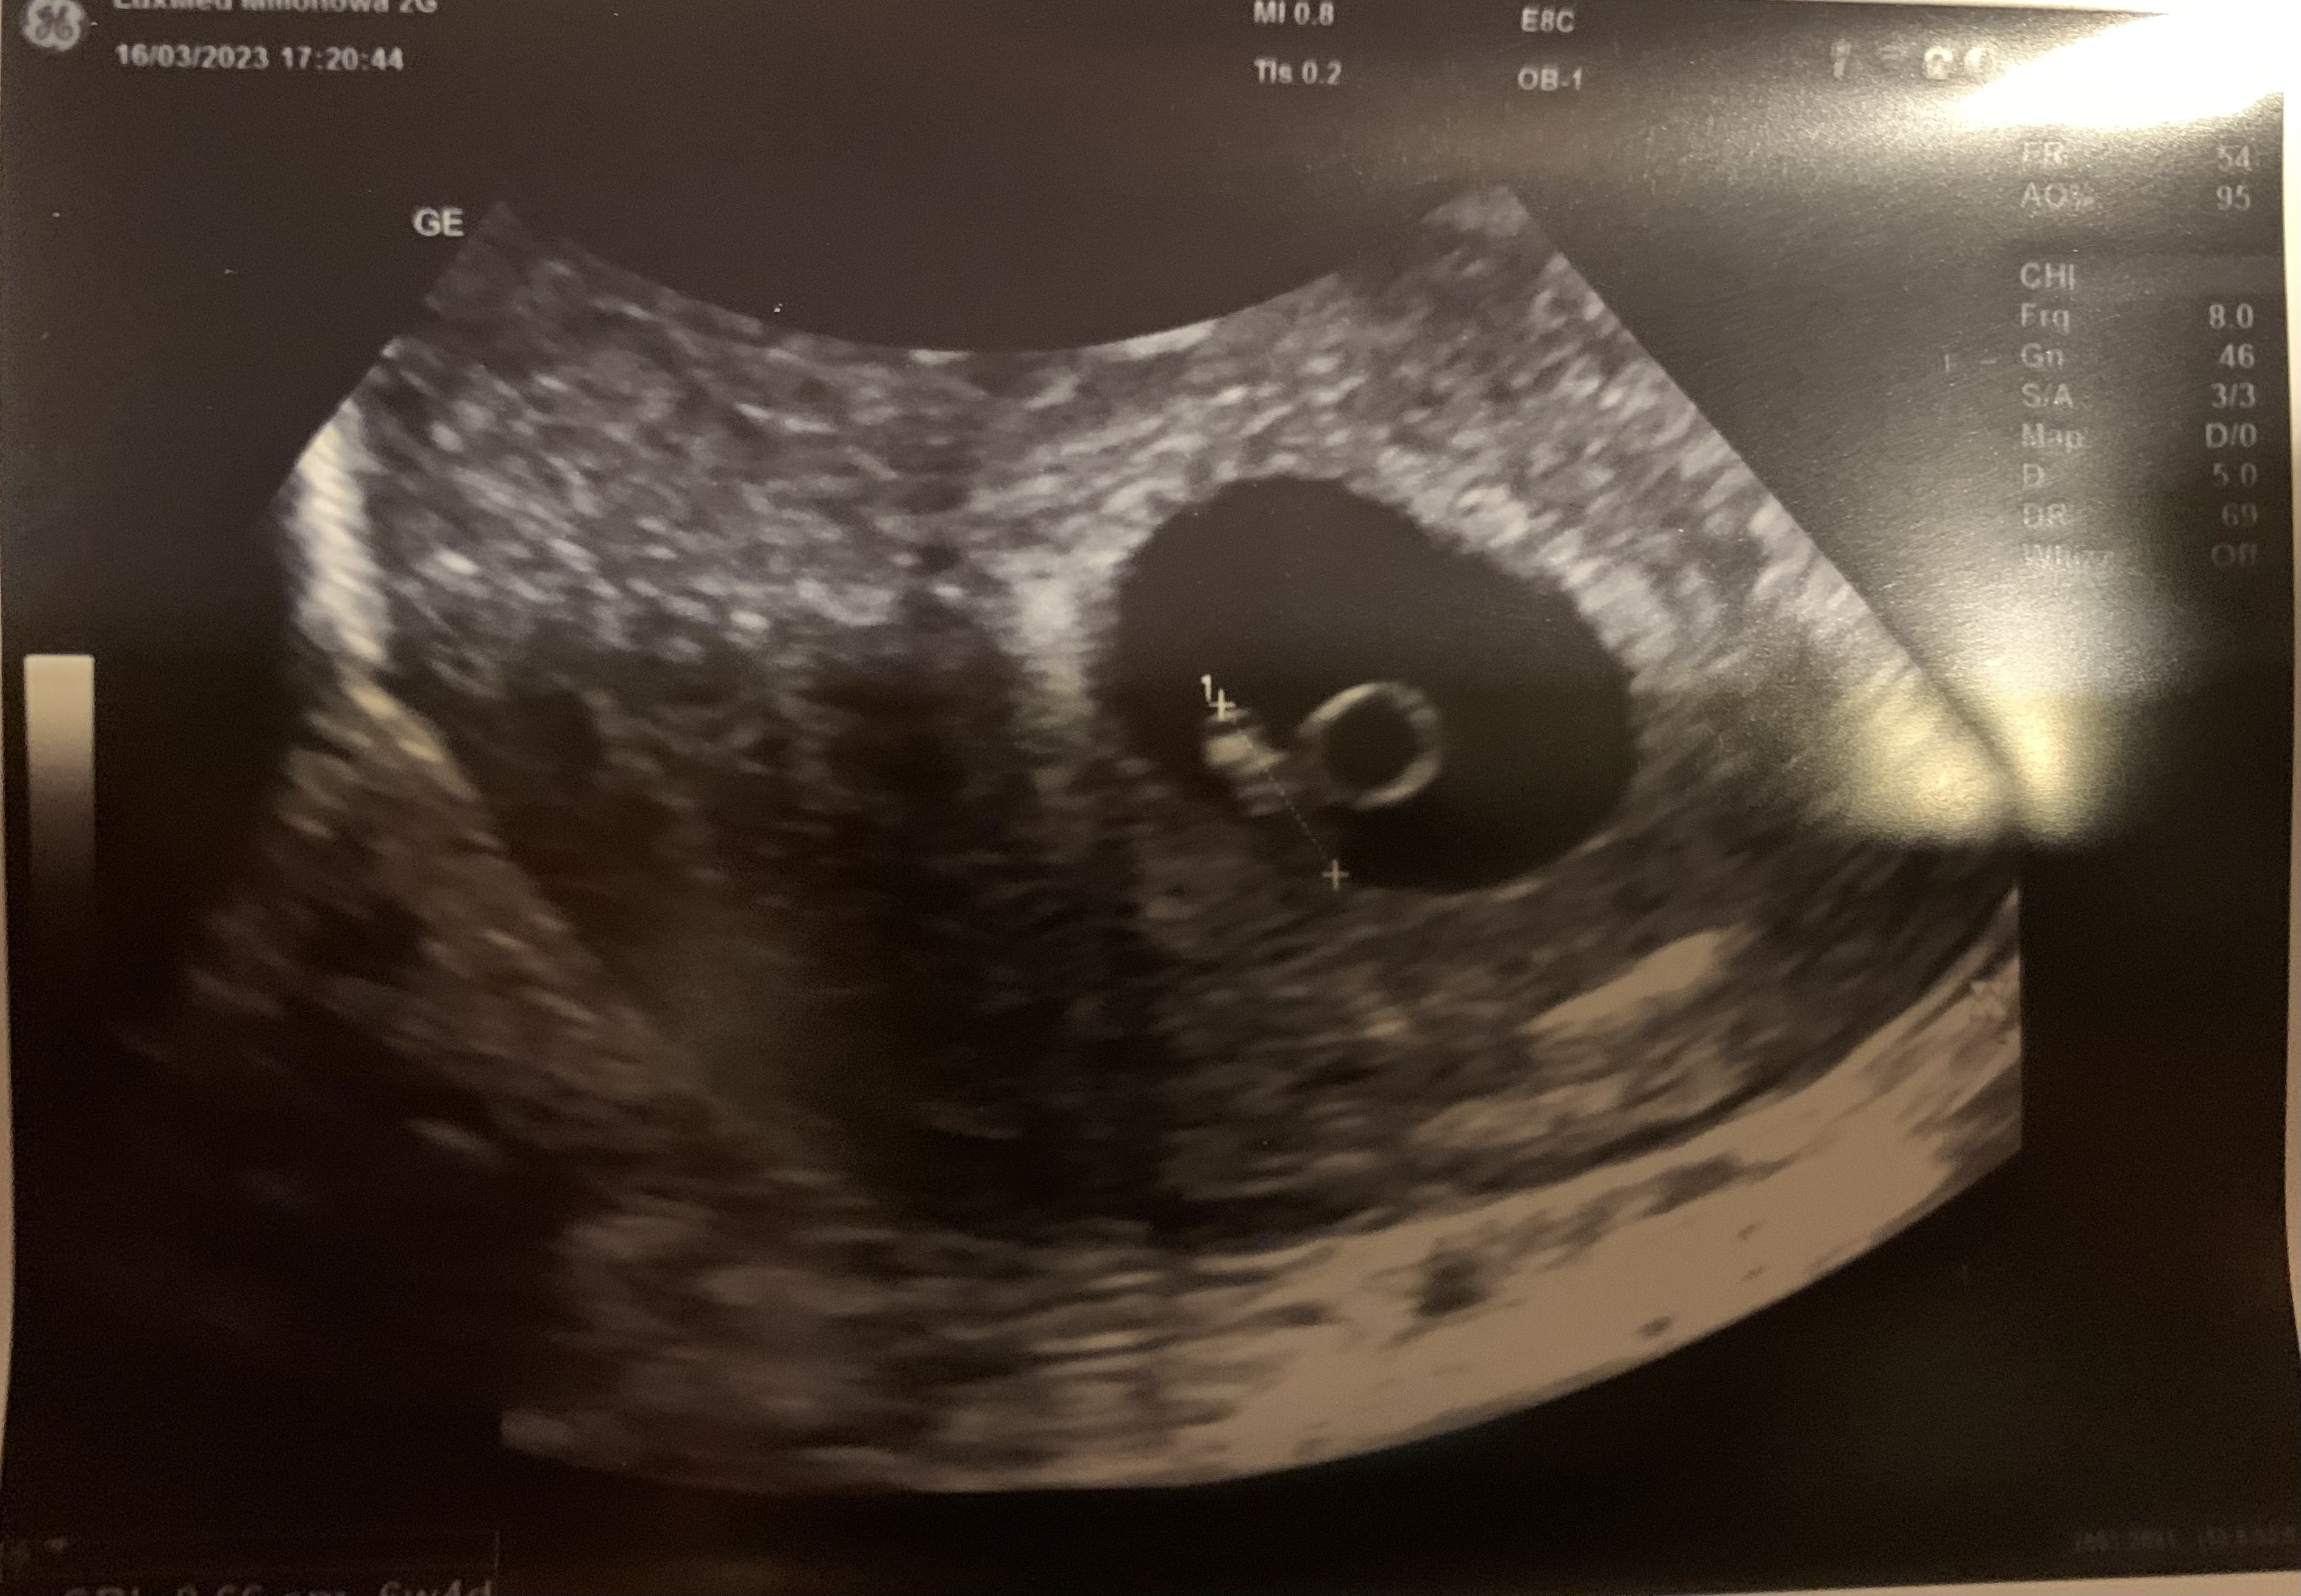

Z wizyty przynoszę dobre wieści, bo jest zarodek z serduszkiem!

No i jeszcze zdjęcie małego purchlaczka zamieszczam, bo prawie zapomniałam! ❤